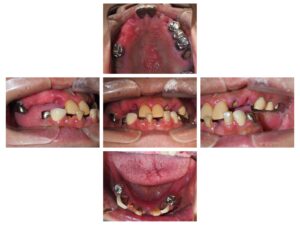

9/3に、全体的に歯を治して欲しいとの事で56歳女性が来院されました。

下顎の前歯部はジルコニアのブリッジ

上下欠損部はノンクラスプのRPIを使った金属床

での計画を立てました。

9/10 ノンクラスプデンチャーを作るため、個人トレーの型取り

9/11 下顎のジルコニアブリッジの型取り

9/24 下顎のジルコニアブリッジset

10/1 上の義歯のset

10/22 下の義歯set

今回も大変喜んでいただけました。